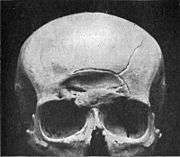

Depressed skull fracture

A depressed skull fracture is a type of fracture usually resulting from blunt force trauma, such as getting struck with a hammer, rock or getting kicked in the head. These types of fractures—which occur in 11% of severe head injuries—are comminuted fractures in which broken bones displace inward. Depressed skull fractures present a high risk of increased pressure on the brain, or a hemorrhage to the brain that crushes the delicate tissue.

Compound depressed skull fractures occur when there is a laceration over the fracture, putting the internal cranial cavity in contact with the outside environment, increasing the risk of contamination and infection. In complex depressed fractures, the dura mater is torn. Depressed skull fractures may require surgery to lift the bones off the brain if they are pressing on it by making burr holes on the adjacent normal skull.[7]